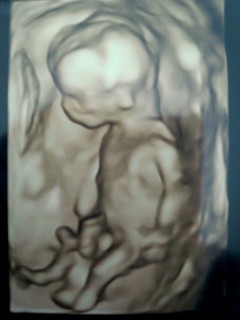

初めての3Dエコー(≧∀≦)

元気に動き回っていて安心しました。

性別判明と、胎動が楽しみです♪♪